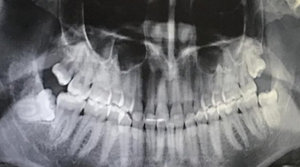

У меня восьмёрка снизу ещё под капюшоном, немного болит. Сделали снимок. Врач предлагает вырезать зуб вместе с костью. Есть ли более щадящий метод удаления или вырезать это нормально?

• 38 зуб расположен таким образом, что полноценно никогда не прорежется, так как частично упирается в ветвь челюсти. Зубы при таком положении рекомендуется удалить. После удаления, лунка закроется слизистой, а в течение 6 месяцев сформируется костная ткань.